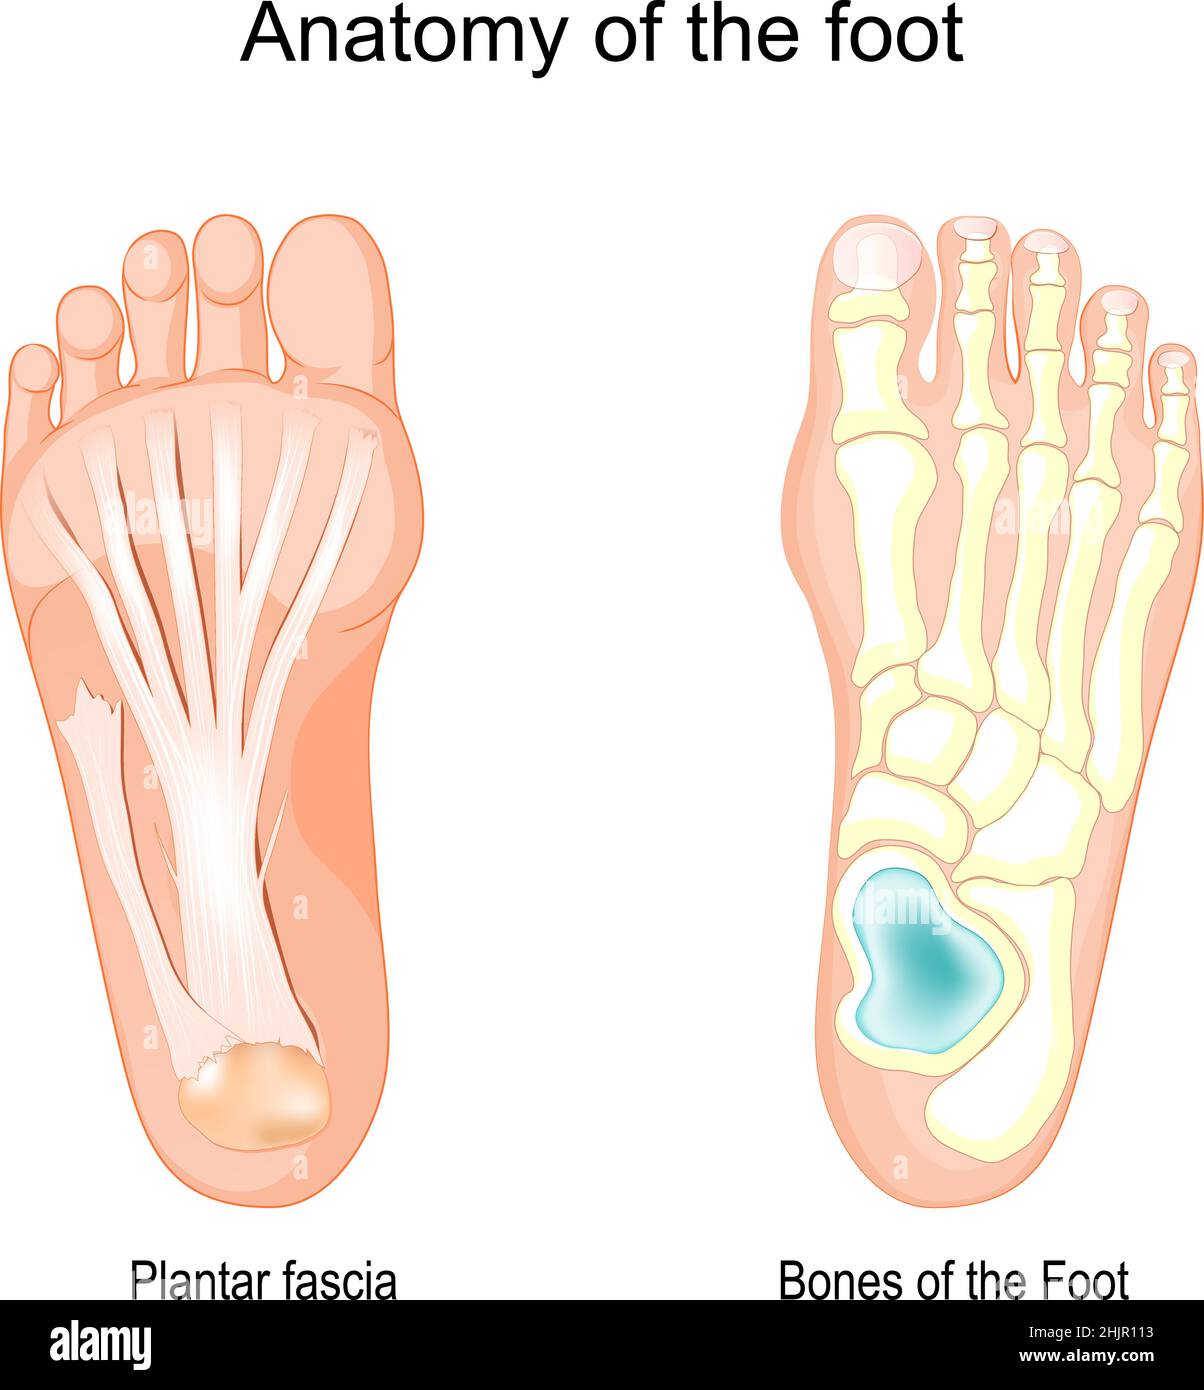

RF2FX3HF0–Fasciite plantaire. Illustration anatomie du pied humain expliquer sur le symptôme fasciite plantaire.